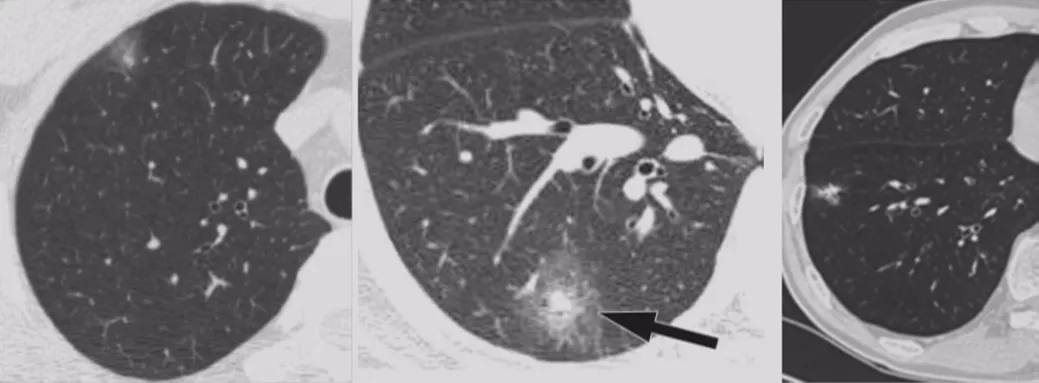

如上图所示,一般来说这么小的病灶我们可能忽略,但这个病人做了手术,不仅是恶性肿瘤,而且是微浸润腺癌。实际上我们在临床上要把这么多结节甄别出来,是十分具有挑战性的。病人一旦患有肺结节,也面临着很多问题,比如焦虑、心理压力等。所以我们既不能过度诊断,但也不能延误诊断。

微小肺结节(肺癌)的诊断价值?

我们刚才看到的征象都是比较典型的。如上图所示的小结节,什么征象都没有,判断为良性也很困难。刚才提到的那么多结节的特征,在微小结节中少见,价值有限。因此,如何提高微小结节的诊断水平是关键,因为在早期手术效果相当好。

微小结节影像特征

国内、国外都有学者做微小结节相关的研究,以上是张国桢教授的书中所描述的征象。肿瘤的生长需要血管,没有供血的话无法生长。肿瘤的供血很丰富,里面血管很紊乱。这个时候如果我们用现代增强CT扫描,用薄层CT、三维重建,可以看到滋养血管进入肿瘤,我们叫做肿瘤微血管移动征。如果「肿瘤血管」增生形成杂乱新生的毛细血管网,我们叫做联通征。这有助于肺癌的早期诊断。